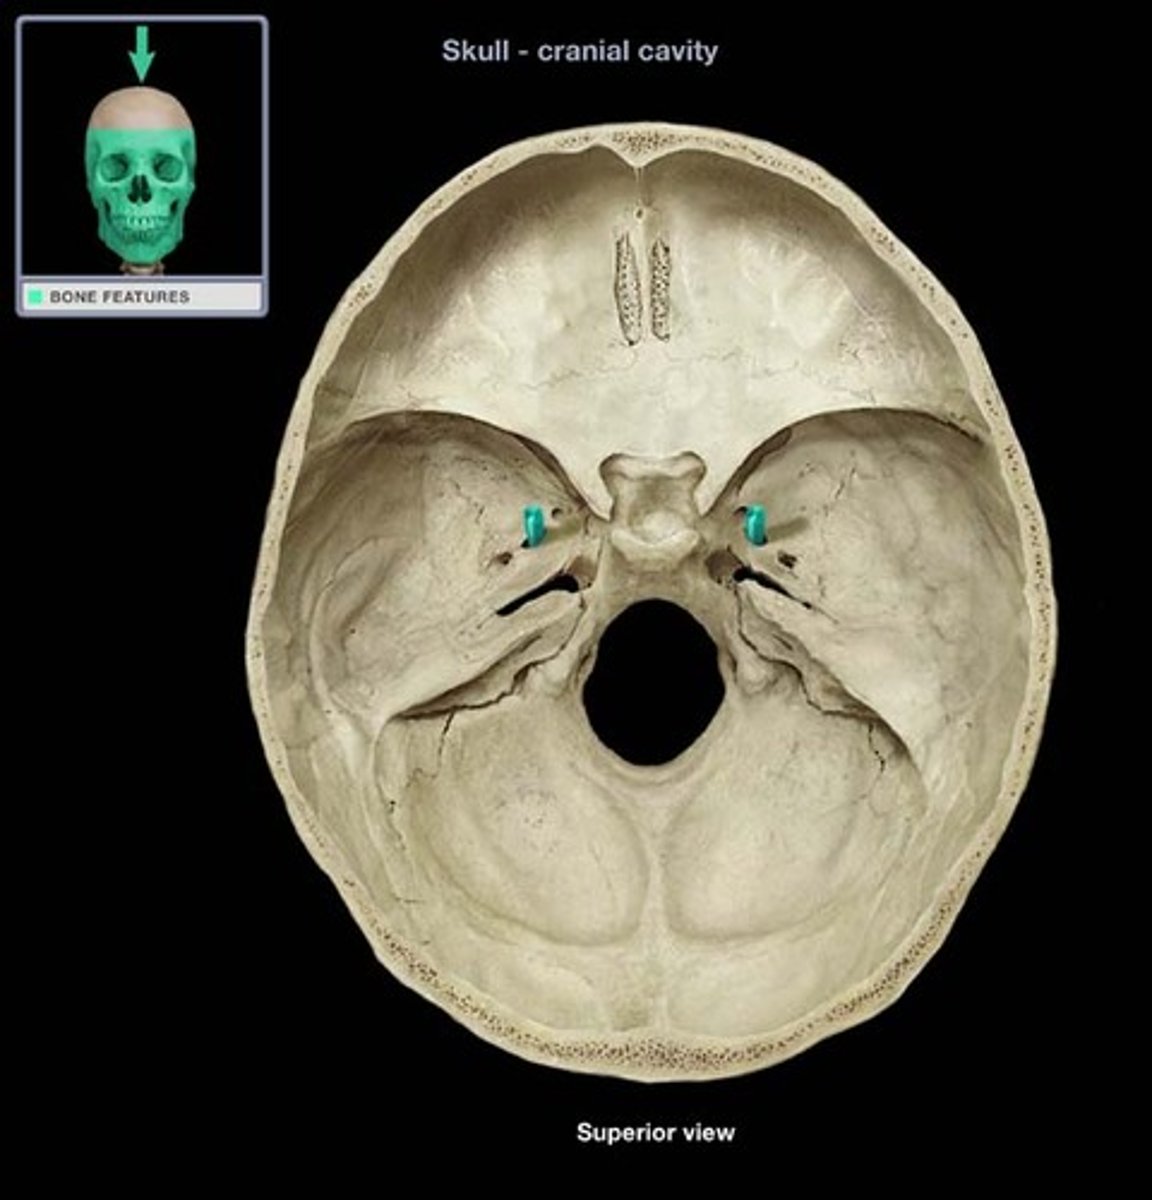

Jugular foramen

Carotid canal